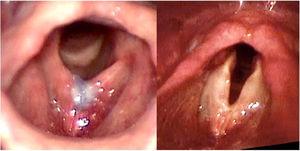

ResultsA total of 7 patients were included. The mean age was 35.4 years (range 27–45 years). The mean time of multidisciplinary monitoring at the service before undergoing glottoplasty was 4.1 years (range 2–7 years). The mean number of weekly sessions of preoperative speech therapy was 24.6 (range 13–54 sessions), with a mean period of 5.7 months. Three (43%) patients underwent glottoplasty in isolation, while 4 (57%) underwent glottoplasty with chondrolaryngoplasty to reduce laryngeal prominence, as reported in a previous case series.32 The mean duration of the surgery was 1:10 h. Fig. 2 presents pre- and postoperative laryngoscopy for patient #5.

ComplicationsPatient #4 developed premature suture dehiscence with no anterior web formation (n = 1; 14%) and failed to raise the pitch of her voice (a drop of 3 Hz in F0), which required a revision surgery. Patient #7 developed a postoperative granuloma (n = 1; 14%), treated with inhaled corticosteroid (Fig. 3). There was no major complication such as dyspnea due to hypertrophic synechia.